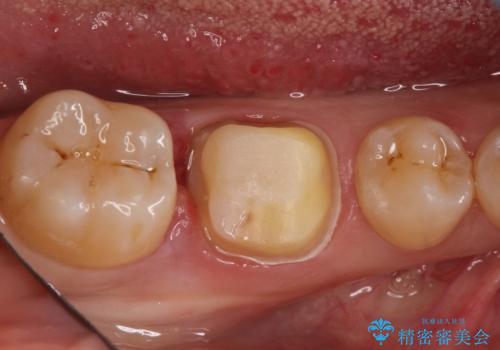

検査の結果、神経は保存不可能と診断されたため、根管治療~オールセラミッククラウンによる治療を行いました。

根管治療を行った歯は破折のリスクが高まるので被せものによる修復が必要になります。

- 13万円(根管治療別途)費用は治療当時の料金となります